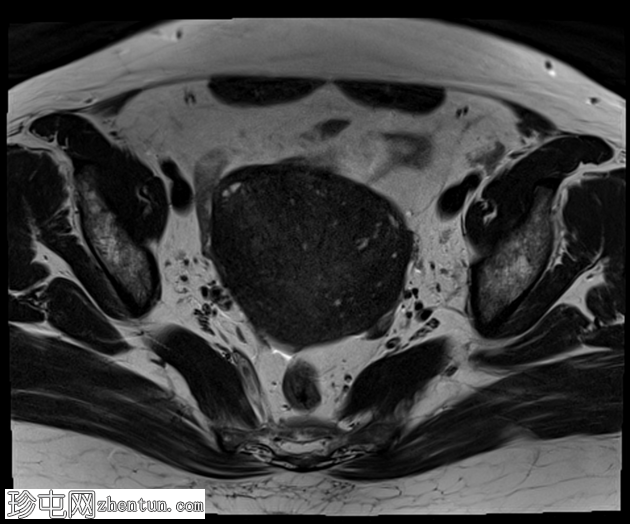

轴位

T2加权像

子宫增大,交界区弥漫性增厚,厚度约2.5 cm,边界模糊,在T1加权像和T2加权像上均可见无数点状高信号灶,提示出血灶。